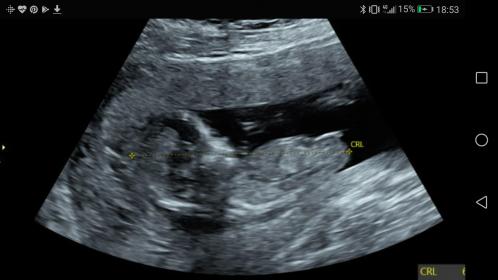

Hi all! I just had my 12 week scan at 12w5d and the tech seemed quite convinced it was a girl (much to my complete surprise because I was sure I'd just have another boy). I've been researching a bit and it definitely seems girly but is it too early to tell really? Is there a chance it will rise? Attachment 39149